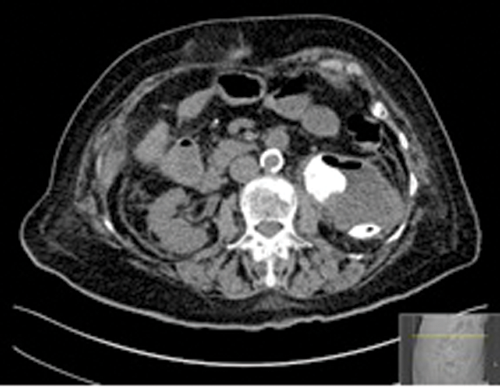

Figures 2: Patient B. Emphysematous pyelonephritis GM.